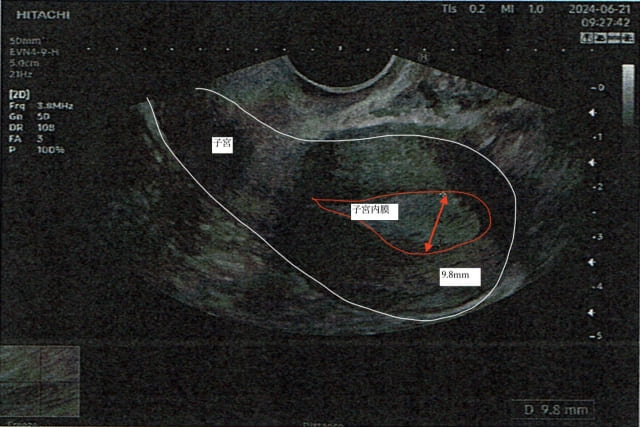

当院の施術で内膜が厚くなる様子

内膜7.7mm

内膜9.8mm(直営よもぎ蒸し併用)当院の施術で良好胚を取得した記録